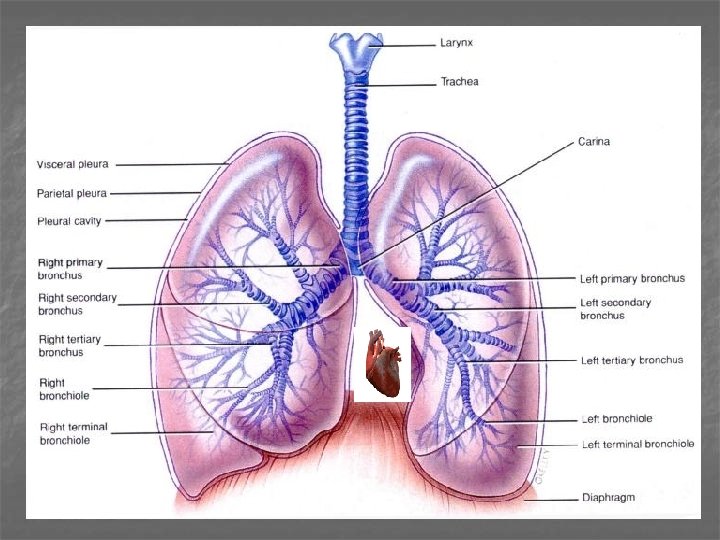

Dýchací cesty (vedou a upravují vdechovaný vzduch): n Dutina nosní n Nosohltan n Hrtan (larynx) n Průdušnice (trachea) n Průdušky (bronchy) n Průdušinky (bronchioly)

Respirační oddíl (transport dýchacích plynů): n respirační bronchiolus n ductus alveolaris n atrium n sacculus alveolaris n alveolus Plicní lalůček (lobulus pulmonalis)

Plíce a bronchy n n Plíce – bronchi principales Plicní laloky – bronchi lobares (sekundární) Plicní segmenty – bronchi segmentales (terciární) 9 – 12 x se větví a zužuje se lumen Ø ≤ 1 mm – bronchiolus: epitel se snižuje, redukce množství pohárkových buněk, žláz a chrupavek

lalok – segment – lalůček plicní pravý a levý ventiluje plicní lalok (3 vpravo, 2 vlevo) ventiluje segment (10 vpravo, 8 vlevo) ventiluje plicní lalůček

Plíce Lobulus pulmonis: tvar pyramidy, V = 1 cm 3 terminální bronchiolus respirační bronchiolus (1 -3) ductus alveolaris (2 -11) saccus alveolaris et alveoli 1 cm 1 x 1 cm respirační oddíl plic